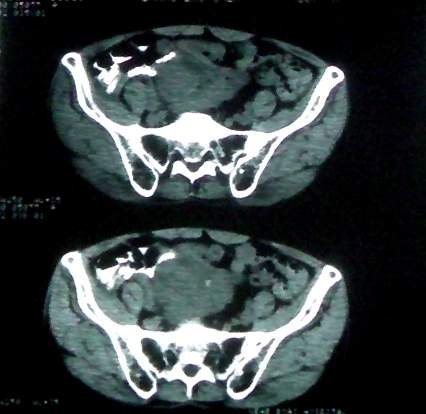

男 60岁,下腹部肿块半年余

腹膜后肿瘤。间叶瘤。

前列腺增大。

盆腔恶性占位,间质瘤可能性大

病理结果:肠系膜肉瘤

肠系膜的原发性肠系膜肿瘤比较少见,大体可分为囊性和实性两类。囊性肿瘤多为良性。实性肿瘤可以为良性和恶性,恶性肿瘤以恶性淋巴瘤为最多,其次是脂肪肉瘤、平滑肌肉瘤、纤维肉瘤等。恶性肿瘤约占实体肿瘤的6% [1] 。文献资料显示原发性肠系膜肿瘤约7%位于小肠系膜,其中60%位于回肠系膜和肠系膜根部,结肠系膜和阑尾系膜仅占20%左右 [2] 。由于肠系膜肿瘤在临床上不多见,症状无特异性,起病隐匿,早期可无症状,只有当肿瘤增大压迫周围的组织脏器时,才有可能出现相应的症状,并且这些症状常与邻近器官受压有关。腹部包块是主要的症状,临床表现为发热、乏力、腹部隐痛不适和饱胀感、消瘦,偶有呕吐及便秘,当肿瘤出血和囊肿突然增大时,可有腹痛,压迫症状有肠梗阻,下肢肿胀,肾盂积水等表现。体格检查时可触及腹部肿块,且活动度好,尤其是横向移动。b超可早期发现腹块,并可确定大小、性质及部位。x线钡剂灌肠检查,虽然不能提供系膜肿瘤的直接诊断依据,可显示为与肠管关系密切之外在性肿物,并可排除肠管、泌尿系等疾病[3] 。腹腔镜对原因不明的腹痛及性质不明的腹块,既可定性又可定位,其正确诊断率为74% [4] 。肠系膜良性肿瘤和恶性肿瘤的病程长短进行比较,恶性肿瘤绝大多数病程均在半年以内,没有超过2年以上。良性肿瘤大多数病程均在2年以上。这一点在诊断上具有鉴别意义。

病灶形态不规则,偏心性裂隙样坏死,支持恶性病变。来源不好定。感谢反馈结果--肠系膜肉瘤。